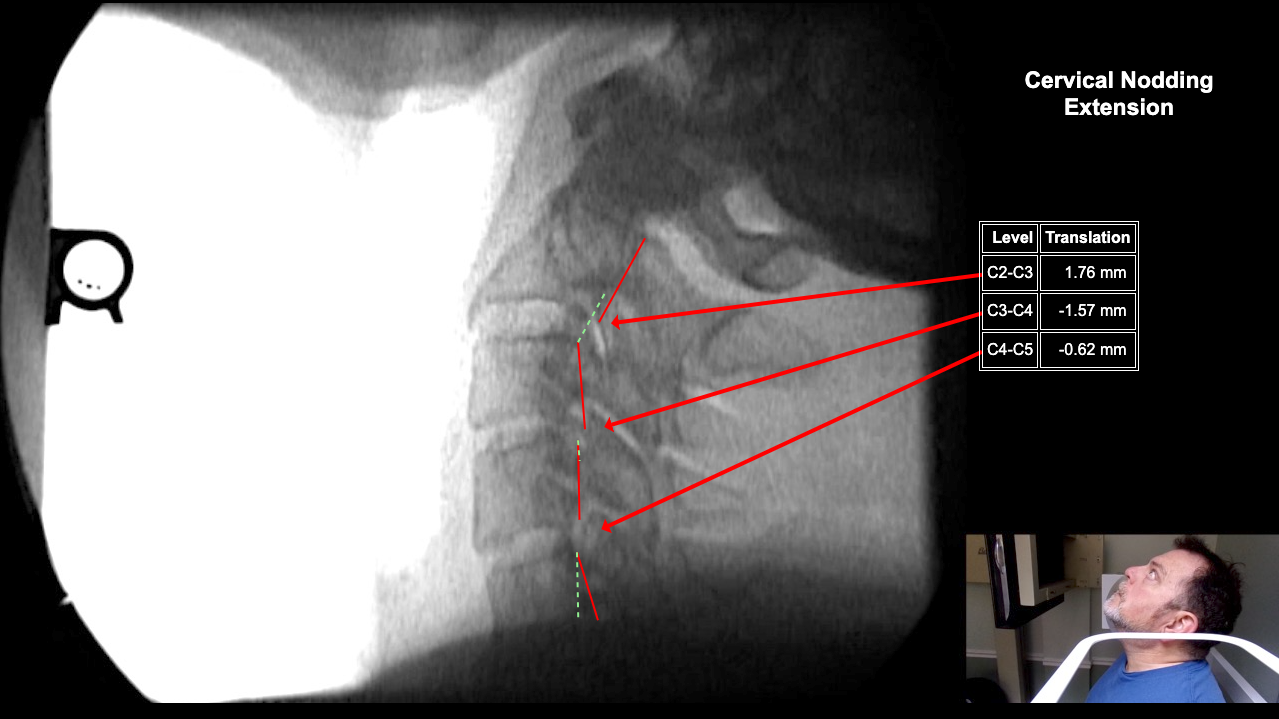

Image 2